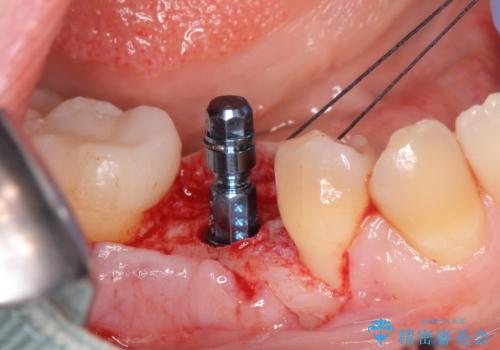

- 過去に抜けてしまった歯のところにインプラントを入れたいとの事で来院。

CTで確認したところ骨の高さや厚みがインプラント埋入できる状態でしたのでインプラント治療を行いました。